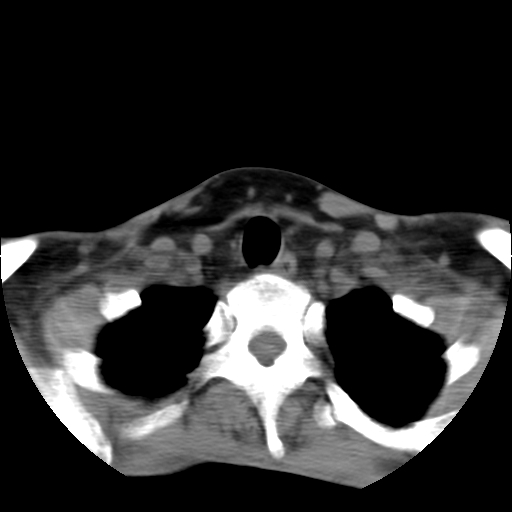

标题: CT24019:男,45岁,发现颈部肿物5个月。 [打印本页]

男,45岁,发现颈部肿物5个月,彩超示:双侧颈部及下颌部软组织增厚。

考虑双侧颈项部良性对称性脂肪增多症。